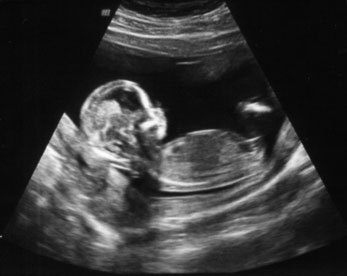

Какие фото УЗИ и живота на 12 неделе беременности? Какой вес и рост плода? - Рой пчел Ответы на все любые вопросы